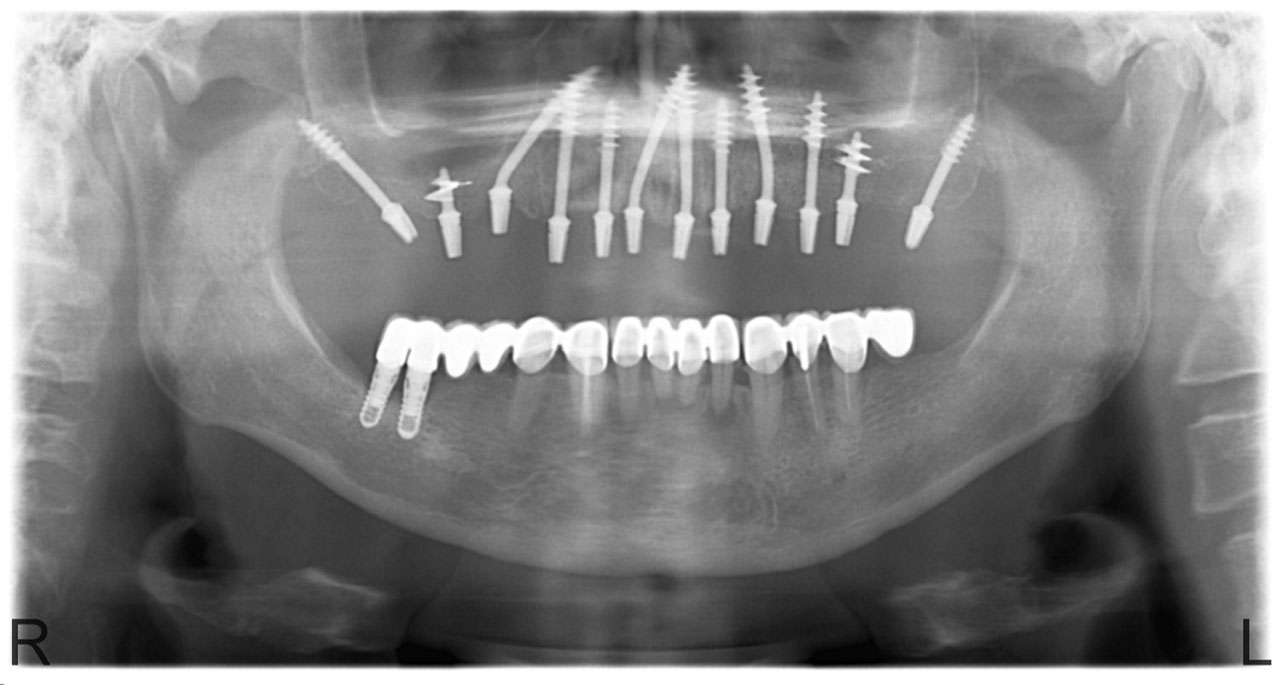

• esettanulmany-03

Imlantáció után,bal oldalon már a végleges hidakkal, jobb oldalon még csak az implantátumok.